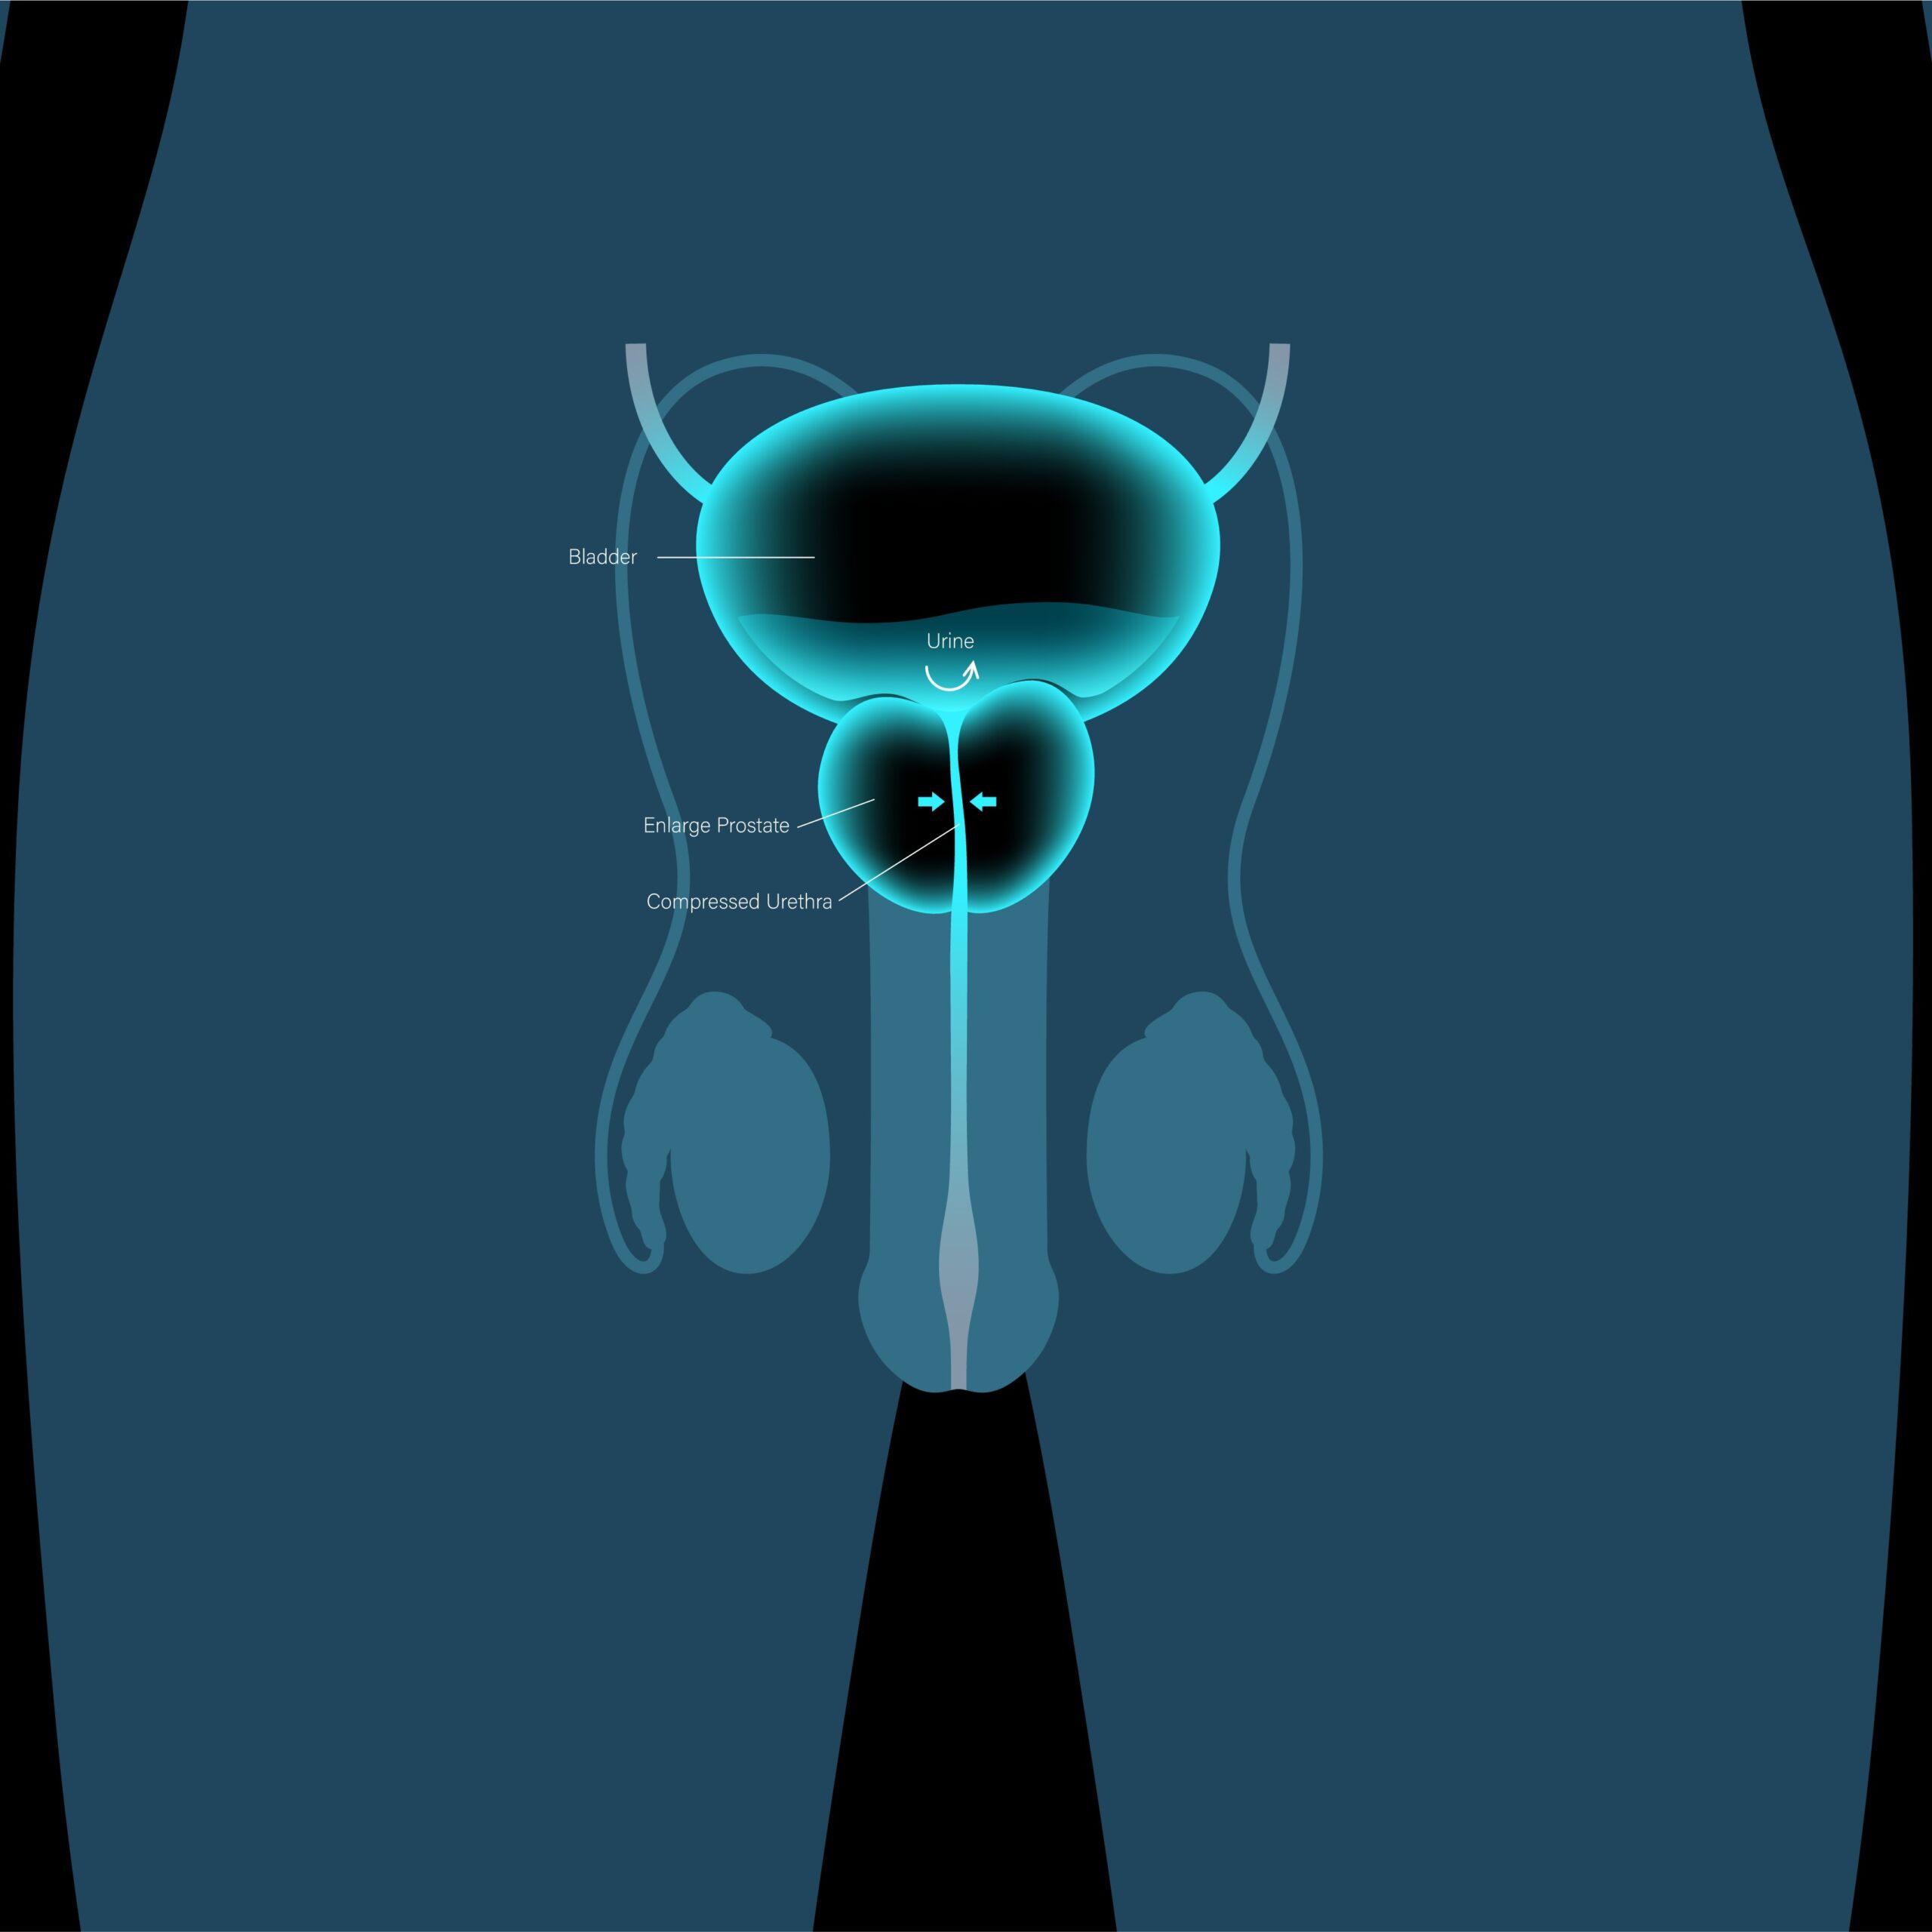

تضخم البروستات الحميد من الحالات الشائعة لدى الرجال فوق سن الأربعين، وينتج عن زيادة طبيعية في حجم غدة البروستاتا مع التقدم في العمر.

- صعوبة في بدء التبول أو ضعفه.

- الشعور بعدم إفراغ المثانة بالكامل.